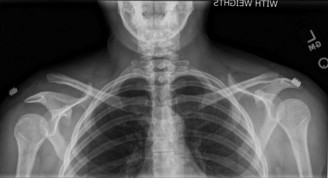

The diagnostic algorithm for a painful total shoulder arthroplasty must be methodical and exhaustive. Initial evaluation begins with high-quality, orthogonal plain radiographs, including a true anteroposterior (Grashey) view, an axillary lateral view, and a scapular Y view. In this patient, radiographs reveal the presence of an anatomic total shoulder construct. Careful scrutiny of the bone-implant interfaces is paramount. While the humeral stem appears well-fixed with no obvious subsidence or radiolucent lines, the glenoid component demonstrates a subtle, 1.5 mm continuous radiolucent line surrounding the central peg and peripheral keels. This finding is highly suspicious for glenoid component loosening, which is the most common mode of mechanical failure in anatomic TSA, but in this clinical context, it raises the specter of septic loosening.

To further delineate the pathology, a CT arthrogram of the left shoulder is ordered. This is the most appropriate next step in management, as established in the primary clinical vignette. The CT arthrogram serves a dual purpose: it provides unparalleled high-resolution, three-dimensional assessment of periprosthetic bone stock and component micro-motion, while the intra-articular contrast allows for the evaluation of capsular integrity and the presence of loosening. If contrast is seen tracking between the glenoid component and the native bone bed, loosening is definitively confirmed. Furthermore, the CT arthrogram is superior to MRI in this specific scenario because standard MRI is heavily degraded by metal artifact (even with MARS protocols), making the assessment of the immediate periprosthetic interface difficult. The CT scan confirms contrast extravasation behind the glenoid component, confirming gross loosening, and demonstrates eccentric posterior wear of the polyethylene, suggesting altered joint kinematics.

Pearl: The CT arthrogram is an invaluable tool in the diagnostic workup of the painful TSA. It provides superior visualization of component micro-motion, polyethylene wear, and capsular integrity compared to standard MRI, which is heavily obscured by metal artifact. Contrast extravasation at the implant-bone interface is pathognomonic for loosening.

Clinical & Radiographic Imaging Archive